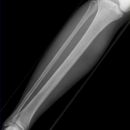

Unterschenkel a.-p. (1. Ebene)

Orthograde Darstellung des Kniegelenkspalts, Patella mittelständig. Distaler Unterschenkel mit Darstellung des Sprunggelenkspaltes.